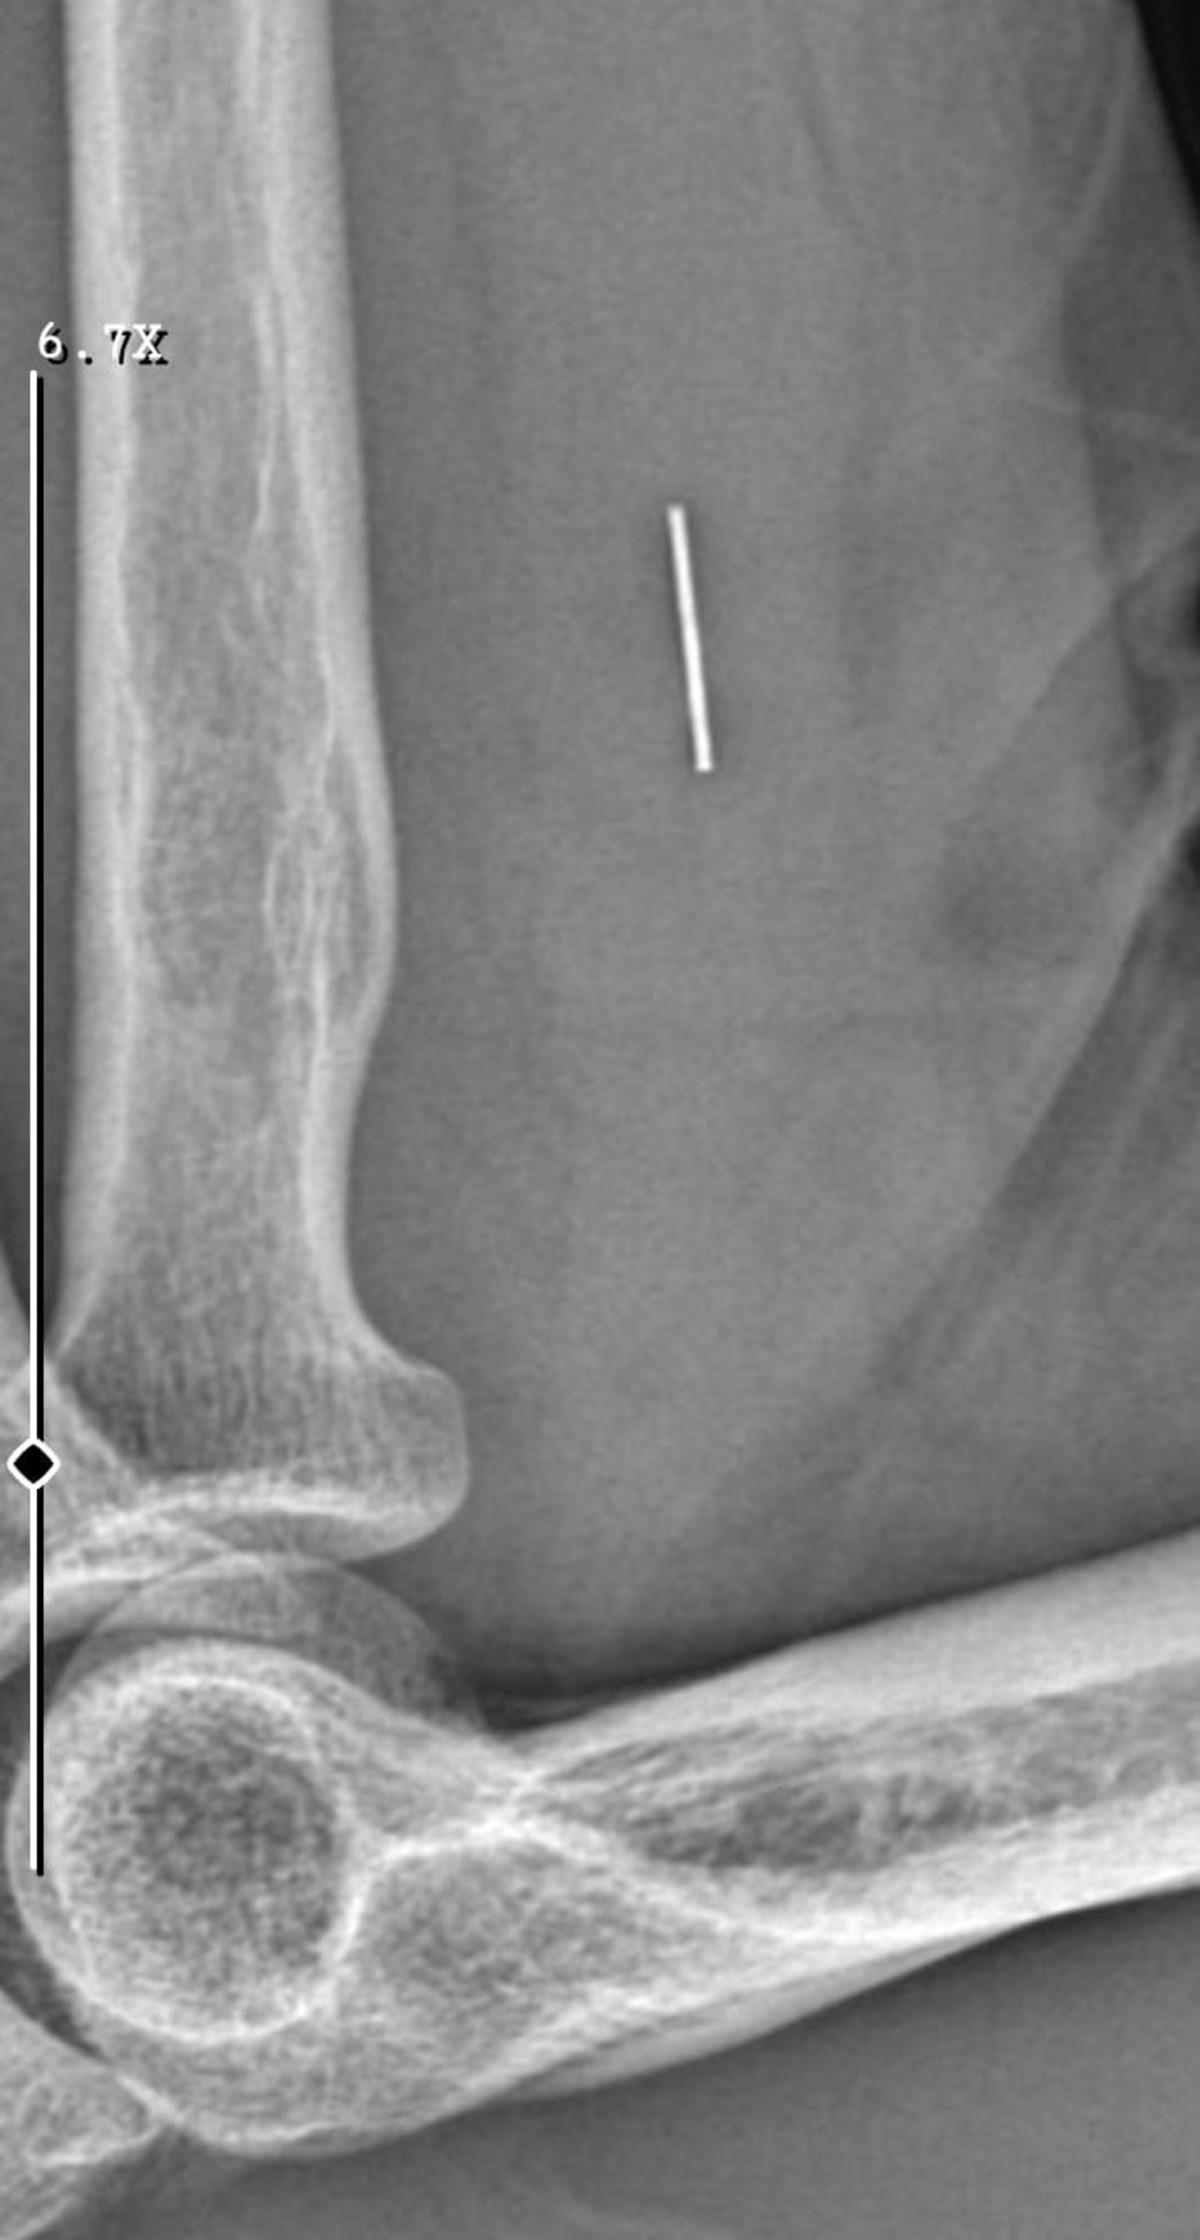

Öte yandan, ameliyatların ardından ağrıları devam eden Güleryüz'ün kolunda metal parça bulunduğu ve bu parçanın parmak bölgesinden dirseğe doğru ilerlediği öne sürüldü. Ayrıca, fabrikada temizlik personeli olarak çalışan Nurettin Güleryüz'ün hastane sürecinde işten çıkarıldığı da öğrenildi.

"Doktorlara bileğime doğru ağrılarım olduğunu sürekli ifade etmeme rağmen beni dinlemediler. Sonradan kolumda metal kaldığını öğrendik. Bunun ihmal olduğunu düşünüyoruz. Çünkü kola metal nasıl girebilir? Ben 9 aydır çalışamıyorum. Kalp rahatsızlığım sebebiyle yüzde 46 engelliyken şu anda yüzde 75 engelli durumuna düştüm. Erken emeklilik dilekçesi verdim ancak henüz sonuç gelmedi. Bu konuda çok mağdurum. Yetkililerin bunu duymasını istiyorum. Savcılığa suç duyurusunda bulunduk. Yaklaşık 9 aydır henüz soruşturma izni gelmedi. Süreci bekliyoruz, henüz dava açılmış değil. Kolumda bırakılan metal ilerliyor. Pazartesi günü bunun için de operasyon geçireceğim. Çıkarılıp çıkarılamayacağı net değil. Elimde titremelerim var, çalışamıyorum ve işveren tarafından işten çıkarıldım. Yetkililerden destek ve konunun incelenmesini talep ediyorum."